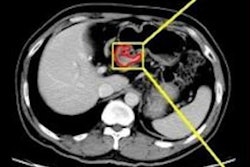

Researchers from China developed a machine learning-based software application to automatically predict lymph node metastasis from the analysis of CT radiomics features. The software was more accurate than radiologist predictions of metastasis based on a conventional staging criterion, they found.

Feng and colleagues sought to develop a machine learning-based automatic clinical decision-support system that could provide preoperative analysis of the risk for lymph node metastasis in these patients by analyzing clinical and imaging data. After retrospectively collecting clinicopathologic and CT imaging data from 490 patients diagnosed with gastric cancer between January 2002 and December 2016, the researchers extracted radiomics features from venous-phase CT images. Of the 490 patients, 297 (60.6%) had histopathologic evidence of lymph node metastasis.

The researchers selected, ranked, and modeled the relevant features using a support vector machine classifier on 326 training and validation datasets. The resulting model yielded an area under the curve (AUC) of 0.804 in the testing and validation dataset and an AUC of 0.764 in the remaining 160 test cases. The group also compared the diagnostic performance of the software with a conventional staging criterion, as assessed on CT images by two radiologists with three years and 10 years of abdominal imaging experience, respectively. The radiologists independently provided their evaluations and were blinded to the clinical and pathological data.